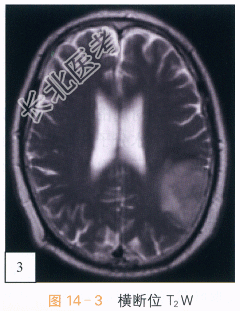

影像学资料:如图14-1~图14-4所示。

读片分析:头颅CT平扫,如图14-1所示,横断位示左颞叶见类圆形等高密度病灶,密度均匀、边界清楚,周围无明显水肿带,肿瘤临近蛛网膜下腔无增宽,脑沟脑回无受压或移位;头颅横断位MRI T₁W像,如图14-2,左颞叶类圆形低信号肿块影,内部信号稍欠均匀;邻近蛛网膜下腔无增宽,脑沟及脑回无明显受压移位;横断位T₂W像,如图14-3所示,肿块呈等高信号影,内部信号略不均匀,无明显囊变坏死及出血;增强扫描后横断位T₁W像,如图14-4所示,病灶强化稍欠均匀;病灶中必可见少许斑片状异常强化,余无明显异常强化,无脑膜尾征。